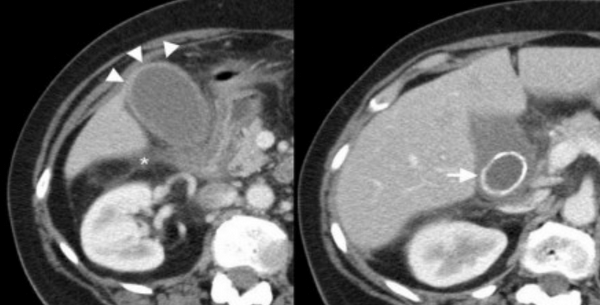

(Слева) На рисунке показан рак желчного пузыря в виде объемного образования в ограниченном участке его стенки, прорастающего в печень и обусловливающего обструкцию общего печеночного протока. В просвете желчного пузыря видны множественные конкременты.

(Справа) На корональной КТ с контрастным усилением визуализируется мягкотканное объемное образование в стенке желчного пузыря, распространяющееся кверху, прорастающее в печень и вызывающее поражение структур ворот печени. Обратите внимание на множественные камни — известный фактор риска рака желчного пузыря. (Слева) На аксиальной КТ с контрастным усилением в желчном пузыре визуализируется полиповидное образование большого размера, накапливающее контраст (рак желчного пузыря). Такие полиповидные образования составляют около 20% всех вариантов рака желчного пузыря, обнаруживаемого на КТ.

(Справа) На сонограмме визуализируется мягкотканное объемное образование (карцинома), заполняющее дно желчного пузыря. Обратите внимание на интактную эхогенную стенку желчного пузыря? отделяющую опухоль от печени, что позволяет предположить отсутствие инвазии печени.